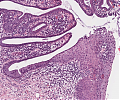

A60 Plattenepithelpapillom

Papillär aufgefaltetes Plattenepithel mit Akanthose.

A68a.jpg

Randbereich des Tumors mit angrenzender Mukosa

-

A68b.jpg

Querschnitt durch den Tumor mit oberflächlicher Ulzeration